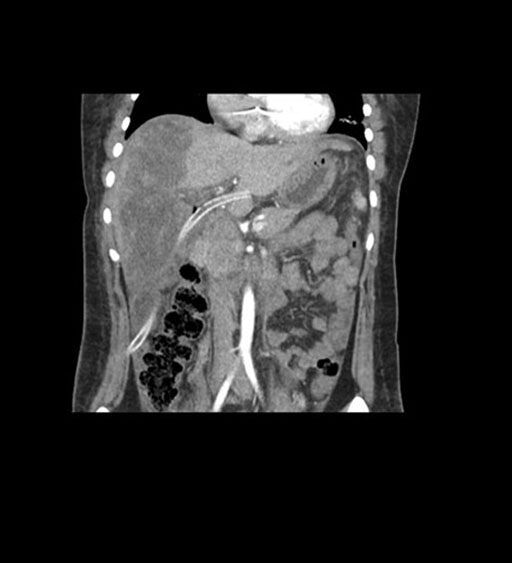

Coronal Venous